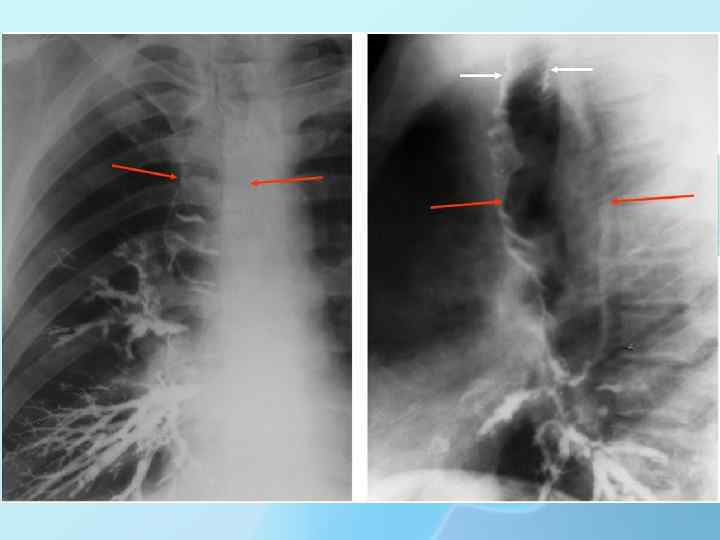

Кистозная гипоплазия (кистозное или сотовое легкое, поликистоз) встречается среди всех пороков развития легкого наиболее часто (в 60 -80% случаев) и сопровождается одновременным недоразвитием бронхов, легочной паренхимы и сосудов с формированием бронхогенных полостей в дистальных отделах субсегментарных бронхов, где обычно развивается хронический воспалительно-нагноительный процесс.